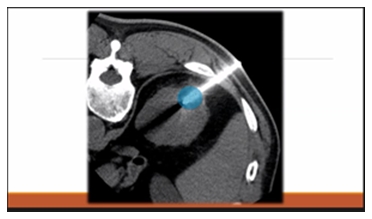

冷冻治疗的针和微波消融的针差不多。在影像设备的引导下,将针插入患者体表,高压氩气在针内循环,针尖的温度迅速下降破坏肿瘤。这种方式与射频消融不同,主要优势在于在治疗实施的过程中可以实时检测冷冻区域。

来自日本国立癌症研究中心中央病院放射科诊断和IVR中心主任-菅原俊佑介绍了“罕见癌症的消融治疗”。消融治疗属于介入治疗IVR ,是在观看超声或 CT 等图像的同时将针从体表插入病灶,通过改变温度杀死癌细胞的一种方式,可以在局部麻醉下进行。具体有两个类别:使用无线电波或微波等高频电磁波将病灶温度提高到 80 ~90°C 来烧灼病变的方法,以及使用氩气将病灶冷冻到约 -160°C以杀死癌细胞的冷冻疗法。医保范畴内的癌症消融治疗中,微波消融治疗仅适用于肝癌,射频消融治疗适用于肝癌、肾癌、乳腺癌、肺癌、骨癌、软组织癌和盆腔内癌症,而冷冻治疗仅适用于肾癌。

微波消融治疗中使用的针比其他消融治疗中的针稍粗。针插入后,消融区域通过电流的功率和时间进行调节。而射频消融治疗时,消融范围根据针的类型进行调整,目前在日本可以消融1~3厘米的范围。